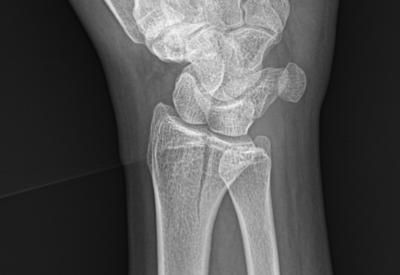

손목 요골 원위부 골절 문의드립니다.

약 3주전 넘어지는 사고로 손목 골절 진단 받고 1주 반깁스 후 통깁스 치료 중입니다.

아래는 사고 당시 X-ray 와 CT, MRI 사진입니다.

• 3번 째 사진

요골 원위부 골절은 골절의 모양, 전위 정도, 관절면 침범 여부에 따라 치료방침이 달라집니다.

엑스레이 및 CT에서 저누이가 심하지않고 관절면에 영향이 없다면 보존적 깁스 치료로도 충분히 잘 붙는 경우가 많습니다. 다만 고령, 골다공증, 분쇄골절, 관절면 불일치 시엔 추후 통증 기능장애 가능성이 있어 수술이 고려됩니다.

• 올리신 사진 세 장을 놓고 진료를 받으신 병원들만큼 자세하게 파악하고 정확한 판단을 내려드릴 수는 없습니다. 사진들을 보았을 때에는 변형이 심하게 생기거나 해 보이지 않기 때문에 손목 가동범위에 문제가 있거나 신경 손상 등을 의심할만한 소견이 없다면 수술적 치료 없이도 회복이 가능할 수도 있겠다 추측해볼 수도 있겠습니다. 그렇지만 앞서 언급하였듯 정확히 어떻다 이야기 하기는 어렵습니다.